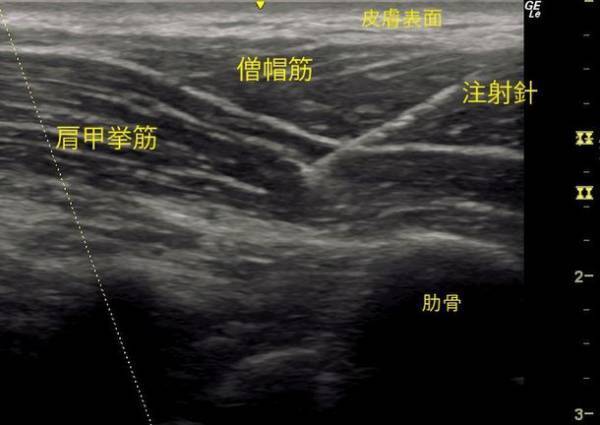

僧帽筋の奥にある肩甲挙筋に針が刺入